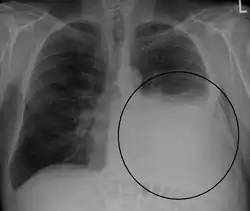

A pleural effusion appears as an area of whiteness on a standard posteroanterior chest X-ray.[15] Normally, the space between the visceral pleura and the parietal pleura cannot be seen. A pleural effusion infiltrates the space between these layers. Because the pleural effusion has a density similar to water, it can be seen on radiographs. Since the effusion has greater density than the rest of the lung, it gravitates towards the lower portions of the pleural cavity. The pleural effusion behaves according to basic fluid dynamics, conforming to the shape of pleural space, which is determined by the lung and chest wall. If the pleural space contains both air and fluid, then an air-fluid level that is horizontal will be present, instead of conforming to the lung space.[16] Chest radiographs in the lateral decubitus position (with the patient lying on the side of the pleural effusion) are more sensitive and can detect as little as 50 mL of fluid. Between 250 and 600mL of fluid must be present before upright chest X-rays can detect a pleural effusion (e.g., blunted costophrenic angles).[17]

Chest computed tomography is more accurate for diagnosis and may be obtained to better characterize the presence, size, and characteristics of a pleural effusion. Lung ultrasound, nearly as accurate as CT and more accurate than chest X-ray, is increasingly being used at the point of care to diagnose pleural effusions, with the advantage that it is a safe, dynamic, and repeatable imaging modality.[18] To increase diagnostic accuracy of detection of pleural effusion sonographically, markers such as boomerang and VIP signs can be utilized.[19]

Massive left-sided pleural effusion (whiteness) in a patient presenting with lung cancer. -